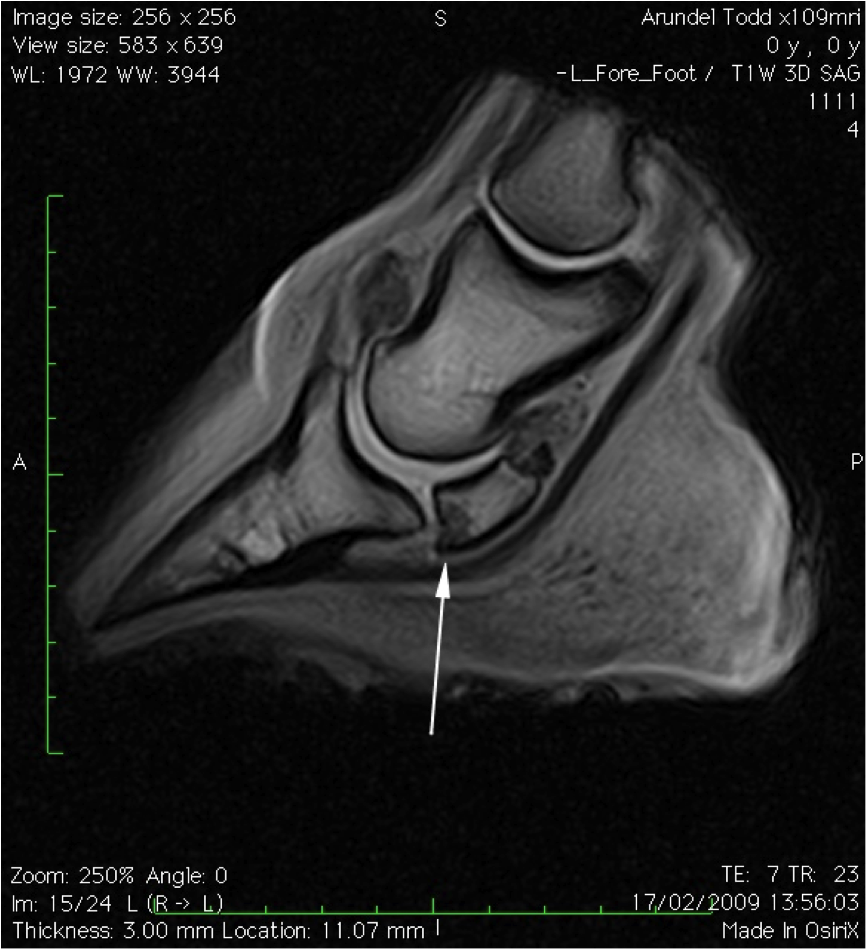

From www.semanticscholar.org

Figure 6 from Treating navicular syndrome in equine patients Horse With Navicular Walking To check your horse for side to side imbalance, simply walk your horse on a flat paved surface. If your horse has heel pain, a problem with his navicular bone is just one of many possible explanations. When a horse starts walking on its toe, especially in the hind leg, it’s a major red flag signaling something is wrong. In. Horse With Navicular Walking.